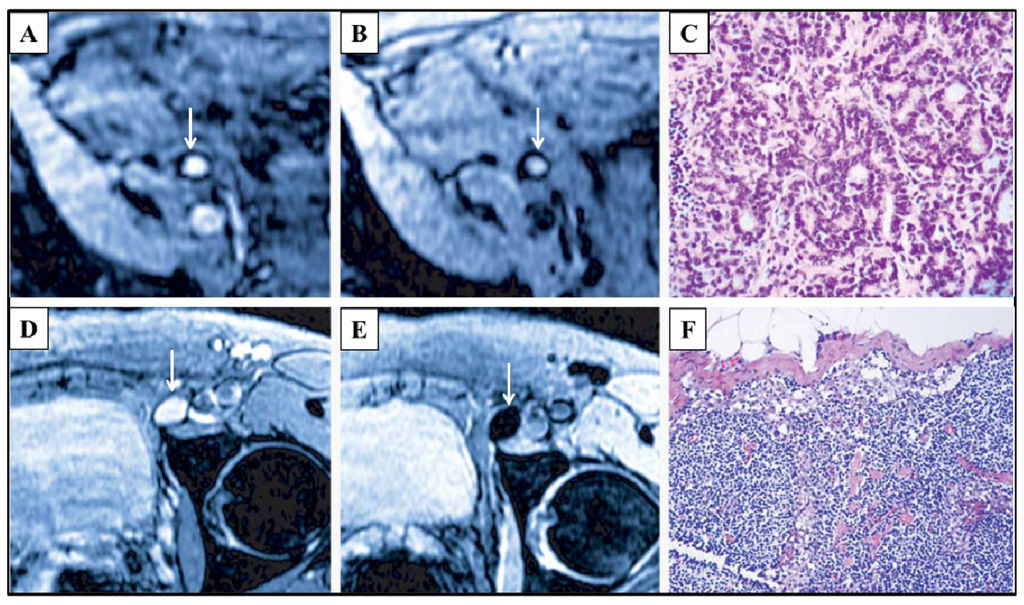

- Harisinghani, M.G.; Barentsz, J.; Hahn, P.F.; Deserno, W.M.; Tabatabaei, S.; van de Kaa, C.H.; de la Rosette, J.; Weissleder, R. Noninvasive detection of clinically occult lymph-node metastases in prostate cancer. N. Engl.J. Med 2003, 348, 2491–2499. [Google Scholar]

- Ross, R.W.; Zietman, A.L.; Xie, W.; Coen, J.J.; Dahl, D.M.; Shipley, W.U.; Kaufman, D.S.; Islam, T.; Guimaraes, A.R.; Weissleder, R.; et al. Lymphotropic nanoparticle-enhanced magnetic resonance imaging (LNMRI) identifies occult lymph node metastases in prostate cancer patients prior to salvage radiation therapy. Clin. Imaging 2009, 33, 301–305. [Google Scholar]

- Guimaraes, A.R.; Tabatabei, S.; Dahl, D.; McDougal, W.S.; Weissleder, R.; Harisinghani, M.G. Pilot study evaluating use of lymphotrophic nanoparticle-enhanced magnetic resonance imaging for assessing lymph nodes in renal cell cancer. Urology 2008, 71, 708–712. [Google Scholar]

- Heesakkers, R.A.M.; Jager, G.J.; Hövels, A.M.; de Hoop, B.; van den Bosch, H.C.M.; Raat, F.; Witjes, J.A.; Mulders, P.F.A.; van der Kaa, C.H.; Barentsz, J.O. Prostate cancer: Detection of lymph node metastases outside the routine surgical area with ferumoxtran-10–enhanced MR imaging. Radiology 2009, 251, 408–414. [Google Scholar]